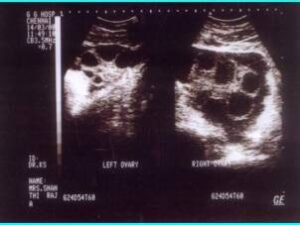

Polycystic ovarian syndrome is the commonest endocrine disorder, and a major cause of anovulation, in women of reproductive age. Patients with this syndrome may suffer from oligomenorrhoea (infrequent menstruation), anovulation, infertility, hirsutism (excessive hair growth), enlarged polycystic ovaries, insulin resistance and hyperinsulinemia and obesity.

Although the primary defect remains unclear, genetic factor is suspected to play a role in the etiology of the disease. About 75 % of anovulatory women demonstrate polycystic ovaries